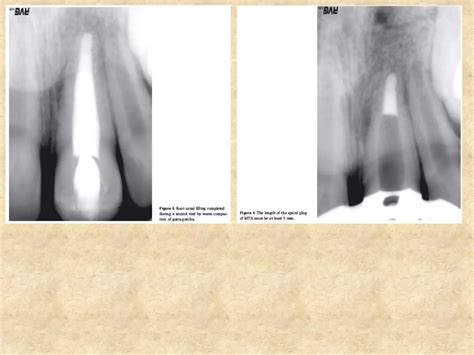

MTA Material In Dentistry Is Saving Teeth That Were Once Hopeless

Saving Natural Teeth with Endodontic Treatment - Leading Edge